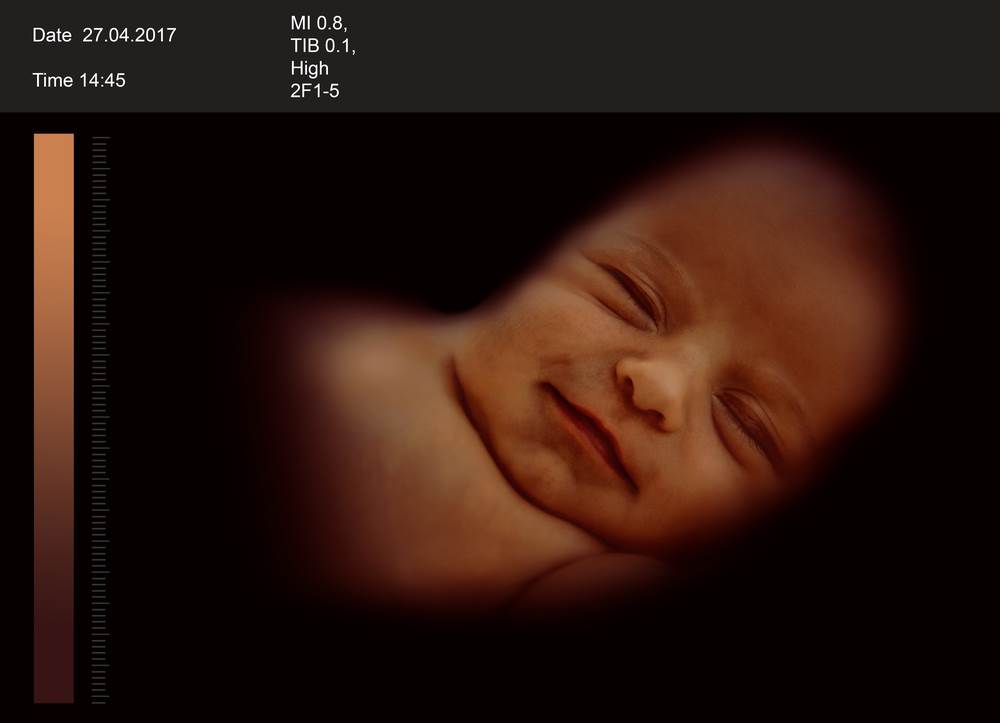

U 25. tjednu sazrijeva bebin sluh. Svaka je buduća majka to već doživjela: uključi li se mikser ili se zalupi vratima od auta, beba u trbuhu se trgne. Bebe u trbuhu rano mogu razlikovati „loše“ od „dobrih“ zvukova. Majčini znakovi ljubavi uvijek su dobrodošli: kada se majka obraća svojoj bebici u trbuhu, ona se umiri i veselo vrpolji. Profesor Manfred Hansmann godinama je proučavao koliko su buduća majka i dijete u njezinu trbuhu povezani: „Zamolim žene da nakon pregleda ultrazvukom još malo ostanu ležati i da glasno razgovaraju s djetetom. Pogledam li netom nakon toga ponovno na monitor, većina beba vrlo opušteno pliva maternicom. Smiruje se frekvencija bebina pulsa, ponekad tu opuštenost čak mogu primijetiti na bebinim crtama lica.“